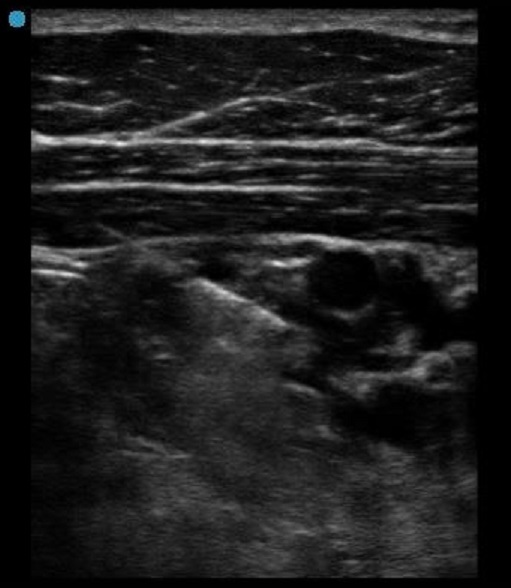

Infraclavicular Post-Injection Image